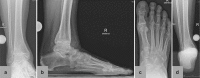

Background: About 1% of adults suffer from painful osteoarthritis of the ankle. The current literature contains no information on the percentage of such patients who derive long-term relief of symptoms from conservative treatment. Advanced ankle osteoarthritis can be treated with non-joint-preserving measures, such as total ankle replacement and ankle fusion.

Conclusion: Total ankle replacement is a good treatment option for complete, end-stage ankle arthritis. It can restore joint function and make the patient mobile with little or no pain. There are, however, many contraindications to be taken into account. There is a need for further studies of the biomechanics of arthritic and replaced ankle joints and for long-term follow-up studies of total ankle replacement.